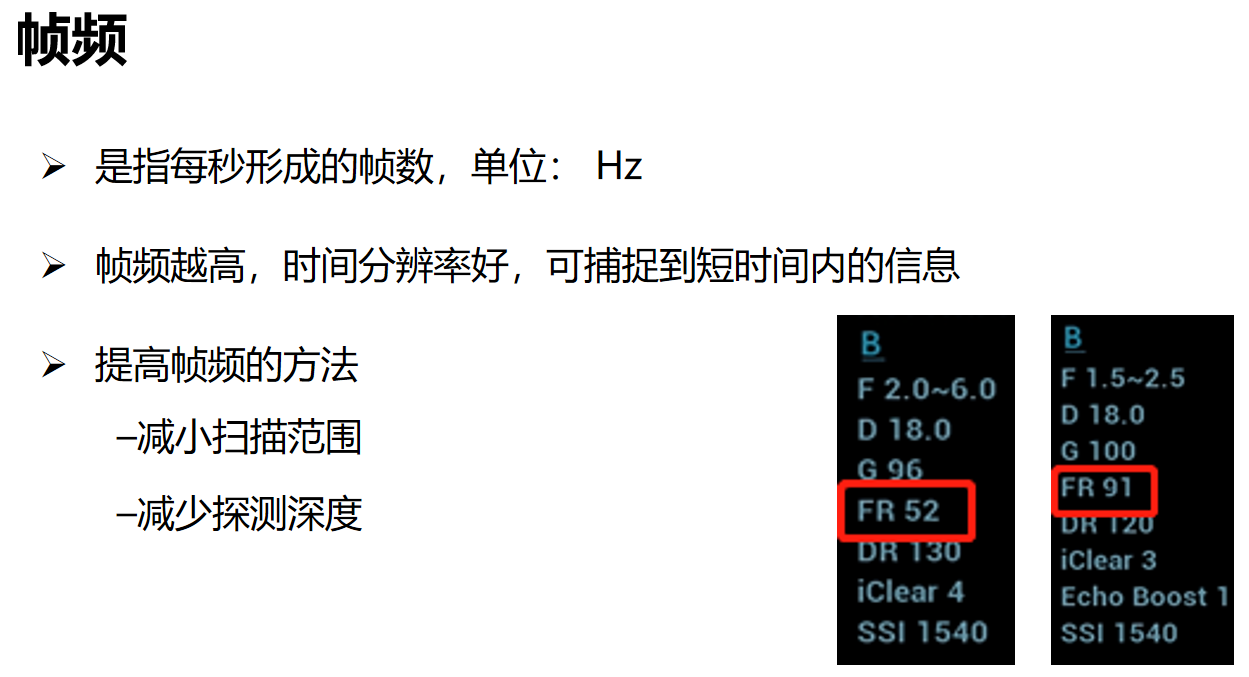

帧频:帧频是指每秒形成的帧数,也就是每秒播放的图像张数,帧频越高,时间分辨率越好。这两幅图分别显示不同的帧频数,一个是52帧,一个是91帧。提高帧频的方法有,减小扫描范围,减少扫描深度。